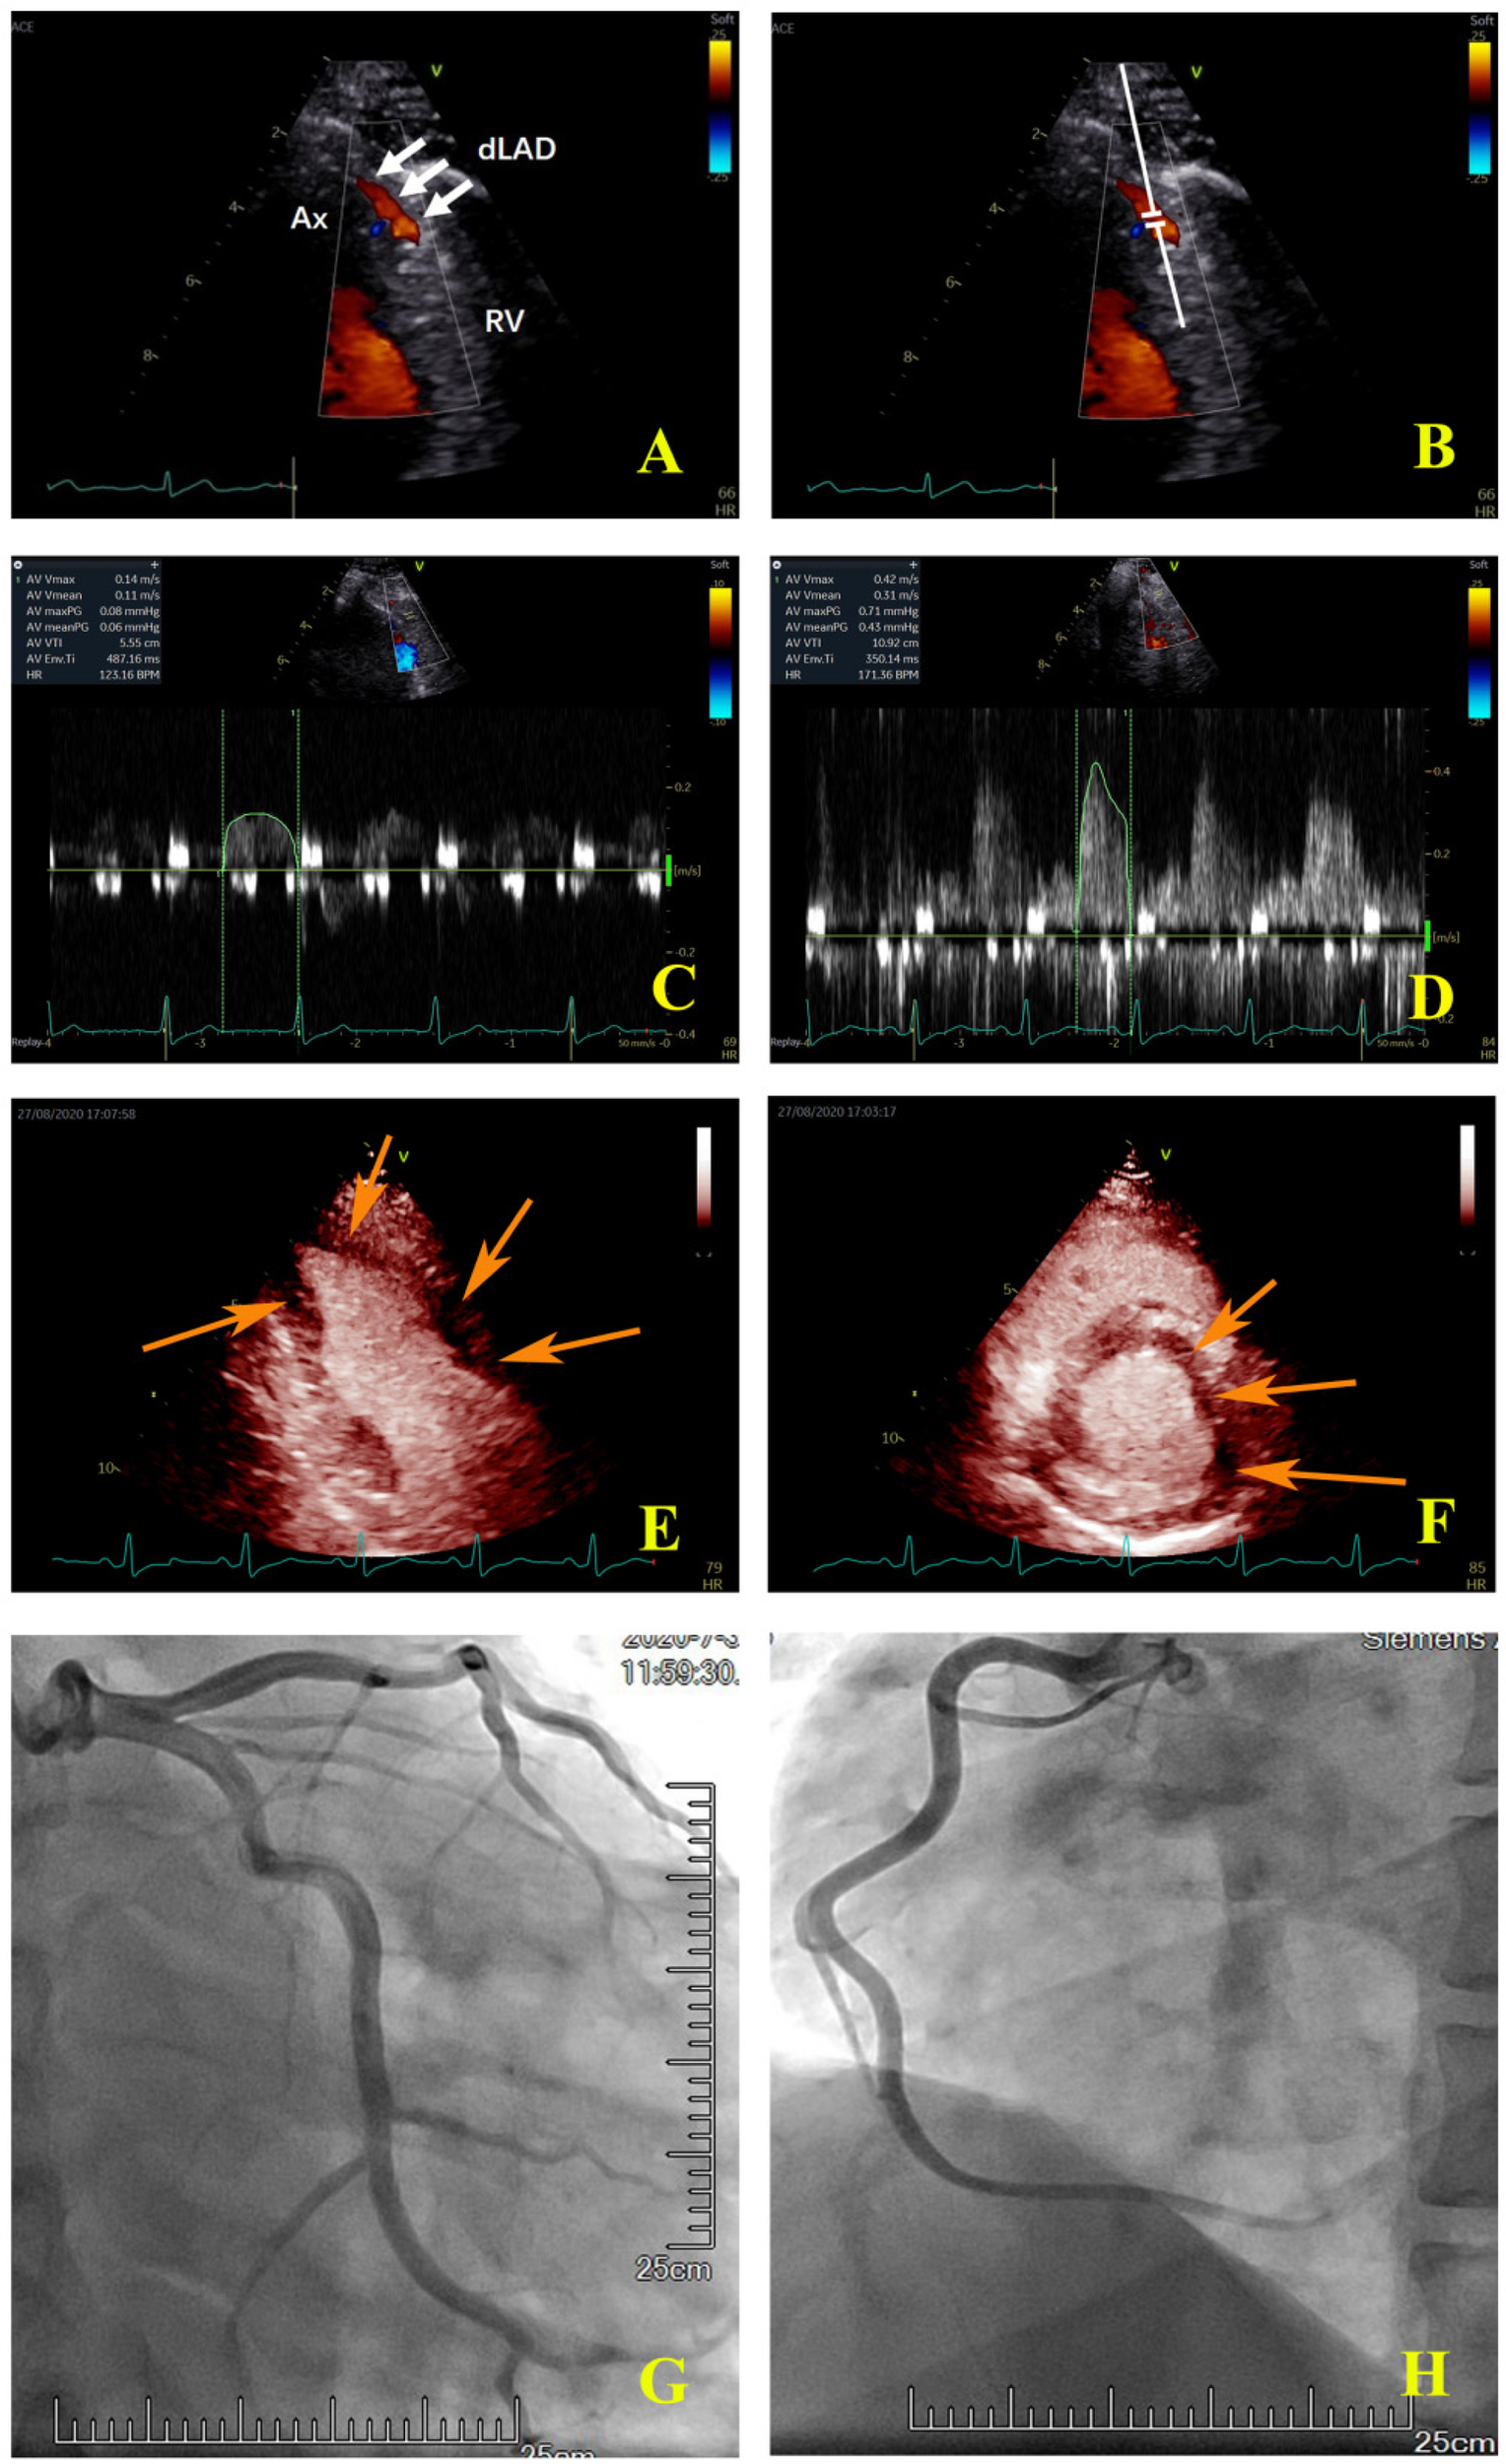

Figure 2

Coronary colour Doppler and blood flow spectrum and MCE and angiographic images of the same patient. (A) The colour Doppler in the distal left anterior descending artery (white arrow); (B) the sample volume was placed in the distal left anterior descending artery; (C) the coronary flow velocity in the distal left anterior descending artery at rest; (D) the coronary flow velocity in the distal left anterior descending artery at peak after stress, CFVR = 2.81; (E) the apical two-chamber view showed that the myocardial perfusion of LV apical and anterior wall was sparse (orange arrow); (F) the middle section of the LV short axis view showed that the myocardial perfusion of the anterior wall and anterior septum was sparse (orange arrow); (G) the left coronary artery angiography. (H) the right coronary artery angiography. Ax, apex; RV, right ventricle; dLAD, the distal left anterior descending artery.

Eleven of the 15 LAD territories (73%) with abnormal CFVR values had abnormal perfusion (Table 3). However, in 20 LAD territories (35%), CFVR was considered normal despite the presence of an induced perfusion defect in the territory (Table 3) (examples are shown in Figure 2 for the LAD territories). In the CFVR vessels with values >2.00, no difference in CFVR was observed for those with abnormal QMP in the LAD territory vs. normal perfusion studies; however, a significant decrease was noted in Rest-Vmean, Peak-Vmean, Rest-Vmax, and Peak-Vmax values (Rest-Vmean: 0.16 ± 0.04 m/s vs. 0.18 ± 0.05 m/s, Peak-Vmean: 0.49 ± 0.14 m/s vs. 0.57 ± 0.15 m/s, Rest-Vmax: 0.21 ± 0.07 m/s vs. 0.25 ± 0.05 m/s, Peak-Vmax: 0.71 ± 0.21 m/s vs. 0.83 ± 0.19 m/s; all p < 0.05) (Table 5).